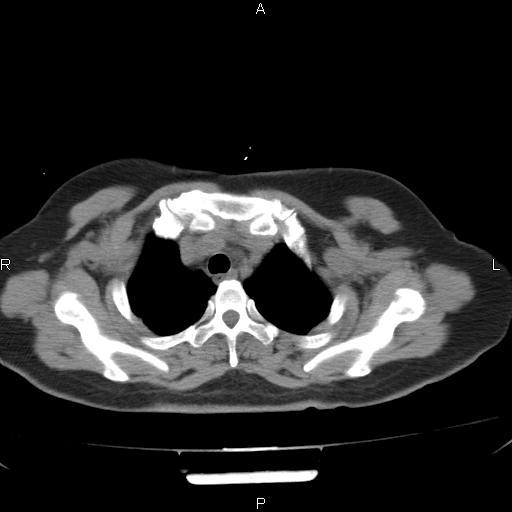

女、63Y 双眼睑下垂,早轻晚重。 胸腺瘤???

结果胸腺瘤